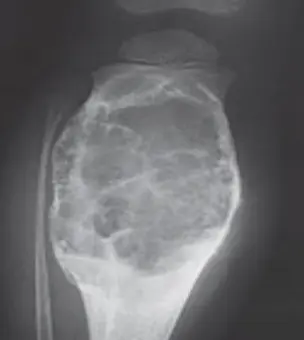

Giant Cell Tumor

Clinical Features:

- Benign but aggressive

- Eccentric and close to the joint line

- Behavior patterns: Benign, local aggressive, high aggressive

- Occurs after fusion of physis